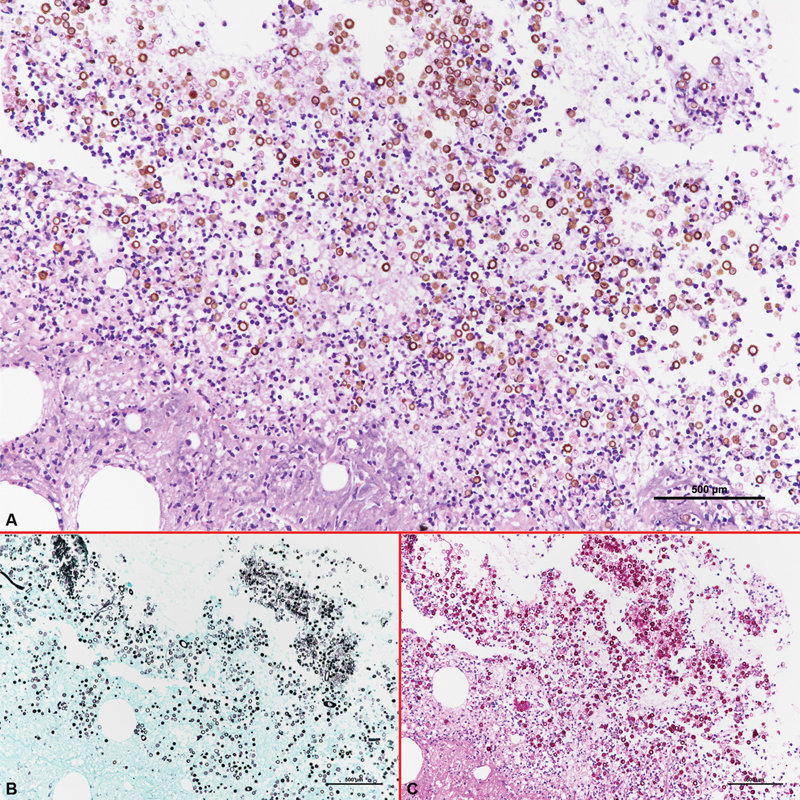

Abstract Image